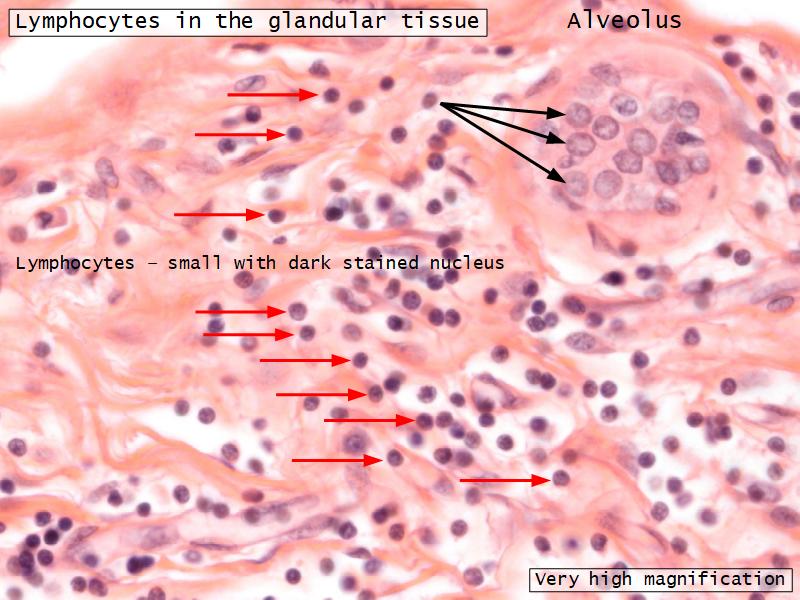

Mammary gland

Write short notes describing the structure of the mammary gland.

(5)

Mammary gland

- Compound tubuloalveolar gland

- 12 - 20 glands

- Each with own lactiferous duct

- Each with own lactiferous sinus

- Opens on skin at apex of nipple

Two stages

- Resting

- Active

Resting and active

Describe the resting mammary gland and compare with the active gland.

(8)

Resting gland

- Connective tissue dominate

- More adipose tissue

- Glandular tissue reduced

Active gland

- Terminal ducts expand

- Forms alveoli

- Connective tissue reduced

- Adipose tissue reduced

- Glandular tissue dominate

Structures

List the structures and cells found in the mammary gland.

Structures

- Lactiferous sinuses

- Stratified squamous near opening on skin

- Stratified cuboidal other parts

- Lactiferous ducts

- Stratified cuboidal

- Myoepithelial cells

- Underlie lactiferous ducts in most areas

- Basal lamina

- Separate epithelial components from stroma

Active gland

- Much larger than resting phase

- Terminal ducts proliferate to form alveoli

- Alveoli

- Surrounded by incomplete myoepithelial cells

Alveolar cells

- Apocrine secretion

- Active state

- Resting state